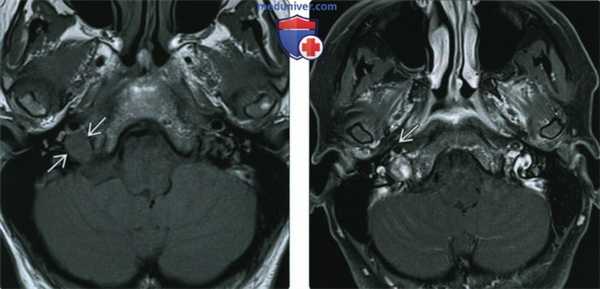

(Слева) При МРТ Т1 ВИ в аксиальной проекции определяется мелкая шваннома правого яремного отверстия. Обратите внимание на характерное отсутствие «пустот потока» вследствие высокой скорости кровотока, что помогает дифференцировать это новообразование от чаще встречающейся параганглиомы яремного гломуса. Мелкие новообразования бывает трудно дифференцировать от асимметричной луковицы яремной вены.

(Справа) При MPT Т1 FS с КУ в аксиальной проекции у этого же пациента наблюдается неоднородное контрастирование шванномы. В крупных опухолях может выявляться интрамуральный неконтрастируемый кистозный компонент.

(Слева) При МРТ Т1 FS c КУ в аксиальной проекции определяется веретеновидная равномерно контрастируемая шваннома правого яремного отверстия, распространяющаяся в соседнюю цистерну. У большинства таких пациентов диагностируется сопутствующая сенсоневральная тугоухость.

(Справа) При корональной МРТ Т1 ВИ FS с КУ определяется неравномерно контрастируемое дольчатое объемное образование, развившееся из яремного отверстия. Обратите внимание на характерное верхне-медиальное направление роста опухоли к стволу головного мозга. В крупных опухолях могут определяться неконтрастируемые участки, представляющие собой интрамуральные кисты.